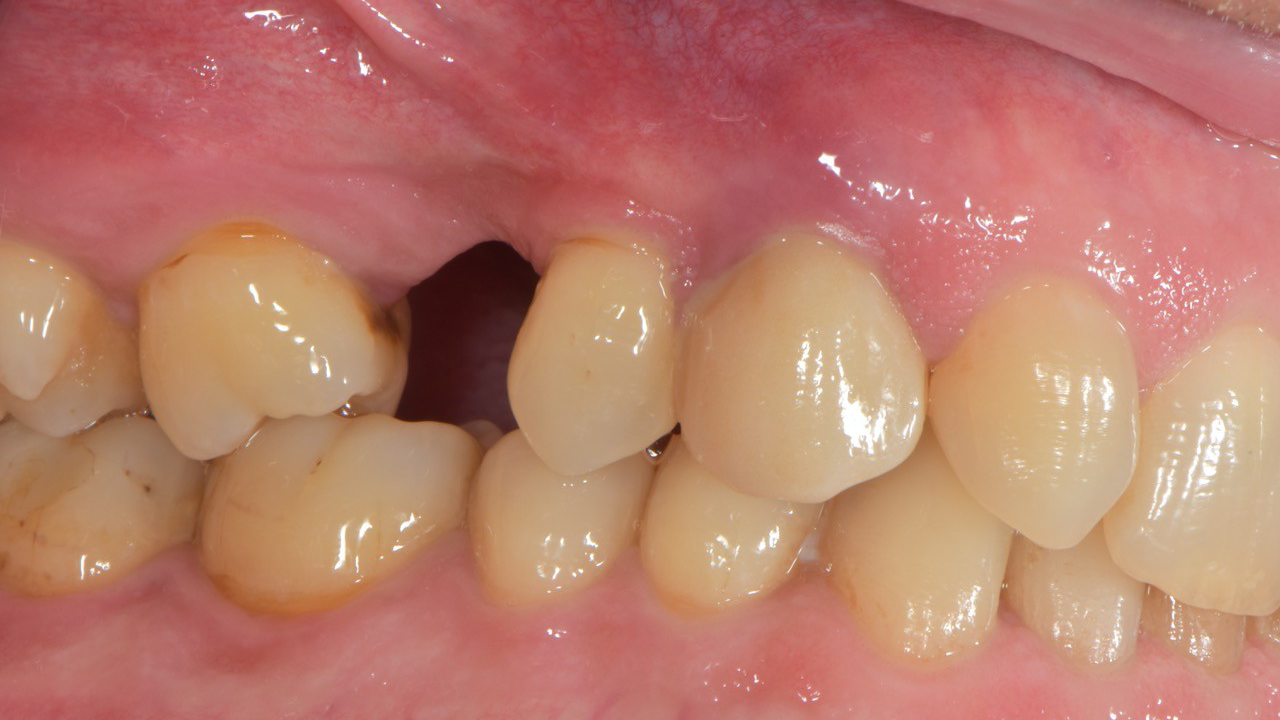

Periimplantitis stellt eine der bedeutendsten biologischen Komplikationen implantatgetragener Versorgungen dar und gefährdet langfristig die Stabilität und Prognose dentaler Implantate. Diese Falldiskussion beleuchtet Pathogenese, Risikofaktoren sowie diagnostische Kriterien und zeigt anhand klinischer Beispiele, wie ein strukturiertes therapeutisches Vorgehen entwickelt werden kann. Dabei werden sowohl nicht-chirurgische als auch chirurgische Behandlungsansätze bewertet und deren Wirksamkeit im individuellen Fall reflektiert. Die Analyse unterstreicht die Bedeutung frühzeitiger Intervention und konsequenter Nachsorge, um den fortschreitenden Knochenabbau zu kontrollieren und eine nachhaltige Implantatgesundheit zu sichern.